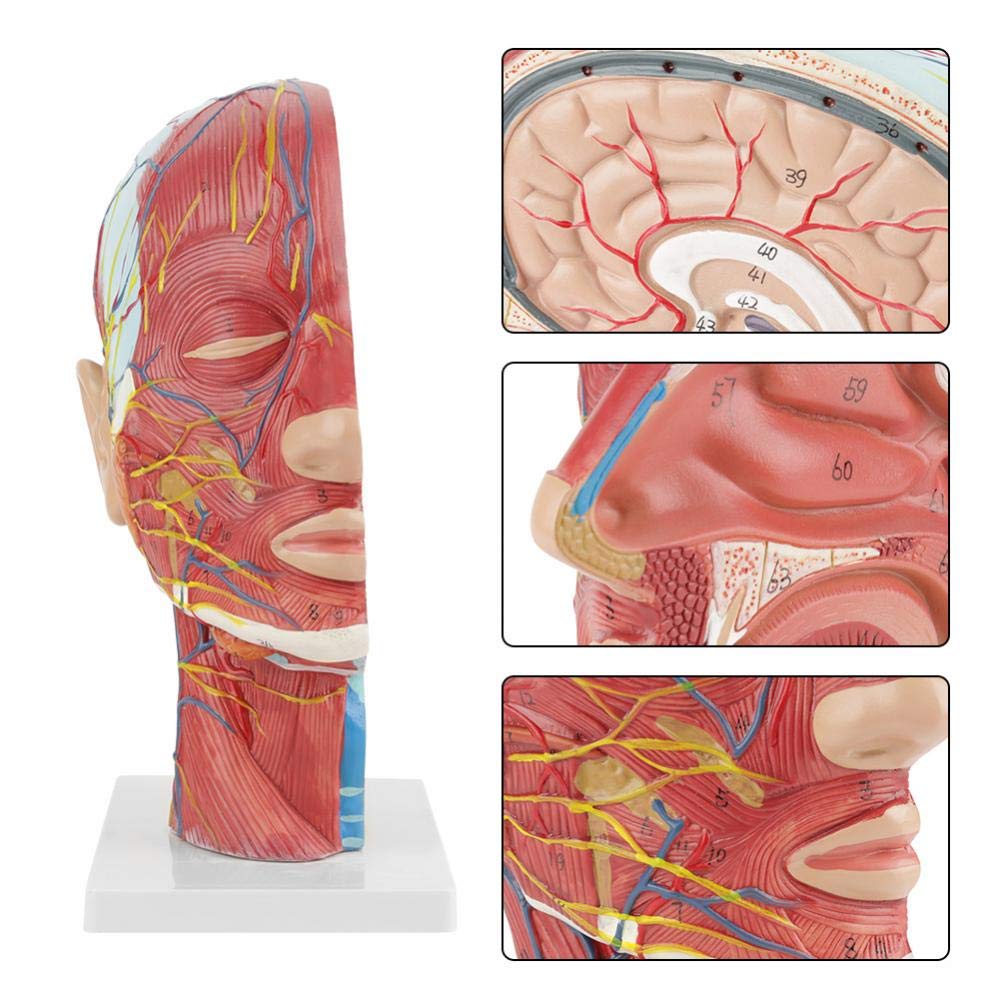

| Izici | Imodeli ikhombisa i-morphology yendawo yezinhlangothi zangaphakathi nezingaphandle zengxenye ye-Median Sagittal yekhanda nentamo, kanye nezinhlaka zemithambo yegazi nezinzwa, futhi kunezingxenye ezingama-84 ezibonisa izibonakaliso zizonke. |

【1: 1 I-Lifesise】 Ingxenye ye-Median ye-Median ye-1: 1 yemvelo enkulu yemvelo & imodeli yemisipha yemisipha ye-nearal ye-nearal ye-nearal (uhlangothi olungakwesokudla). Umsebenzi omuhle. Ukunikeza uhla oluphelele lwezici ze-anatomical.

【Imodeli ye-Neurovascular yemisipha ekhethekile enemininingwane eminingi, izinombolo ezimakwe kakhulu, izindlebe ezivinjelwe, zijulisa ukuqonda kwemisipha engaphezulu, imikhumbi, izinzwa kanye nezinhlaka zangaphakathi zekhanda nentamo. I-Red-artery, i-Blue-Vein, i-Yellow-Nerve.

Izici 【Izici】 Kubonisa izicubu ezingezinhle zobuso obudaluliwe; Imithambo yegazi engekho emthethweni nezinzwa zobuso ne-scalp; Izakhiwo ezingaphakathi ze-Parotid Gland & Upper Respiratory Tract; isakhiwo sesigaba se-sagittal somgogodla wesibeletho.

Le modeli ikhombisa imininingwane yekhanda leNhloko yeNhloko yeNhloko ne-Mid sagittal yomuntu. kufaka phakathi okuphezulu

izicubu zobuso obudaluliwe; Imithambo yegazi engekho emthethweni nezinzwa zobuso nesikhumba; Izakhiwo ezingaphakathi

ye-parotid gland nepheshana lokuphefumula elingaphezulu; isakhiwo sesigaba se-sagittal somgogodla wesibeletho.

Le modeli ikhombise i-morphology yendawo yezingxenye zekhanda nentamo yekhanda nentamo kanye nezinhlaka zayo ze-vascular nezinzwa, ezinazo ingqikithi yezinkomba eziyi-100.

Le modeli iyinhloko enkulu yemvelo nemodeli ye-neurovascular yemisipha eyindilinga, isakhi esingu-1, ekhombisa imininingwane yekhanda lelungelo lomuntu kanye nentamo kanye nengxenye ye-Median Sagittal, okubandakanya imisipha engemihle yobuso, imithambo ephakeme yobuso obukhulu bobuso kanye nesikhumba, izinzwa nokwakheka kwempilo kwe-parotid gland kanye nepheshana lokuphefumula elingaphezulu, kanye nesakhiwo seSigaba se-sagittal somgogodla wesibeletho